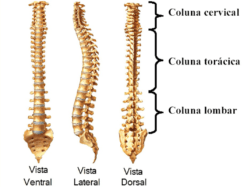

Podemos dividir a coluna em três partes: região cervical, torácica e lombar. A lombalgia é caracterizada por uma dor na região lombar, localizada perto da bacia. A dor pode irradiar para as nádegas, parte posterior das coxas e não muito além do joelho.